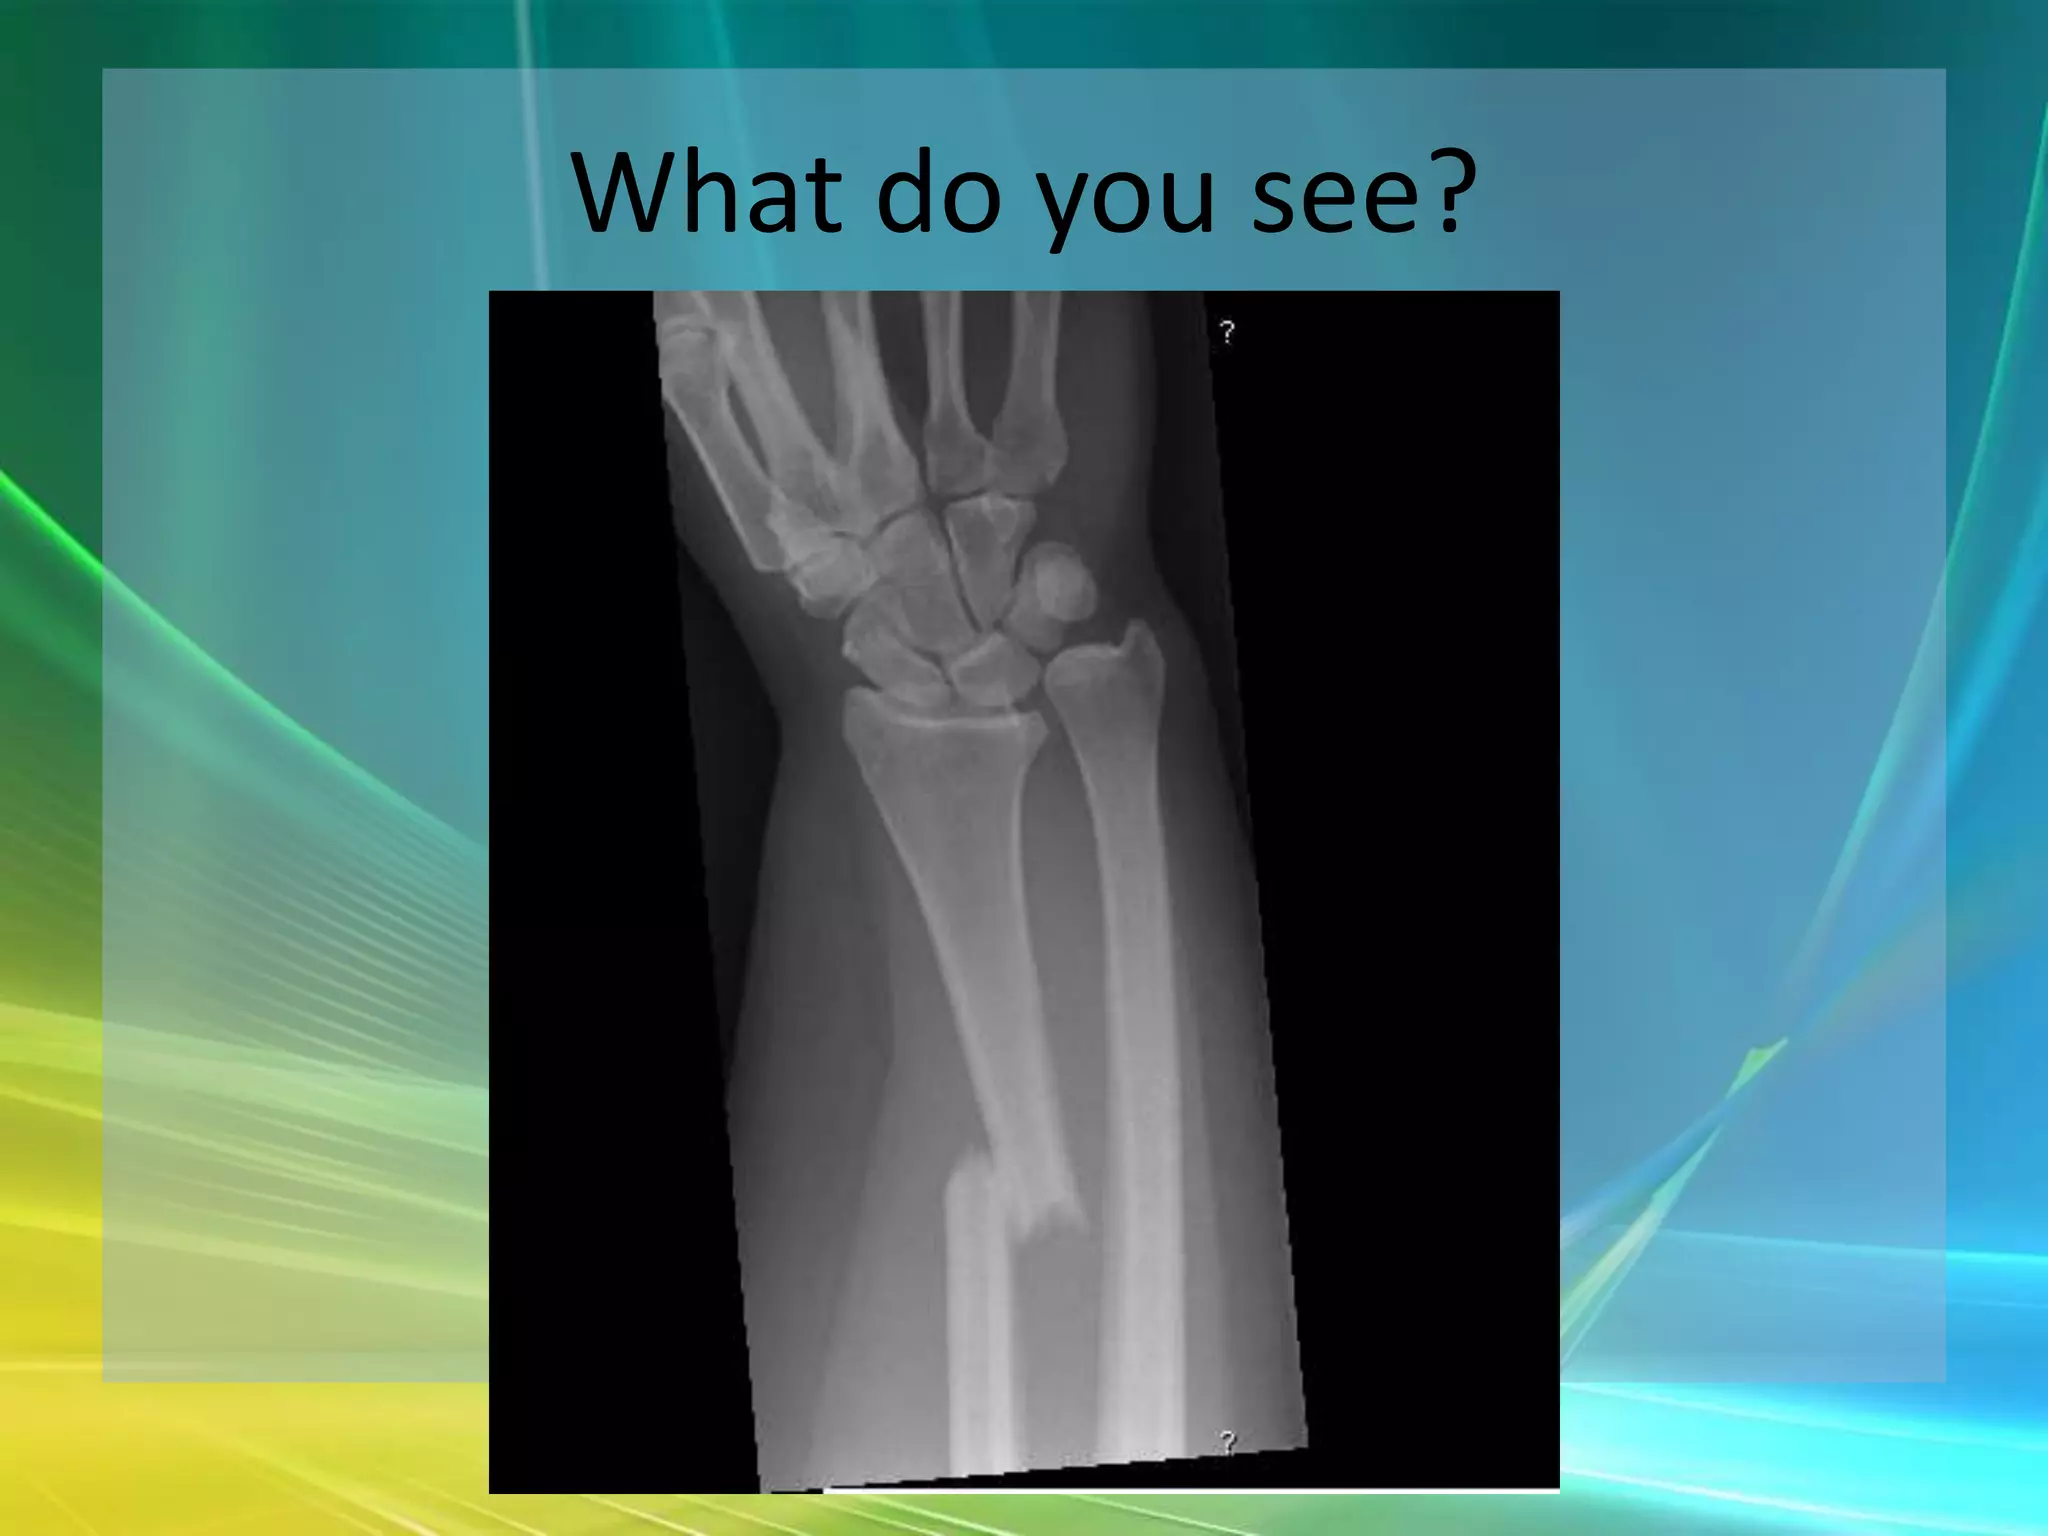

What do you see?